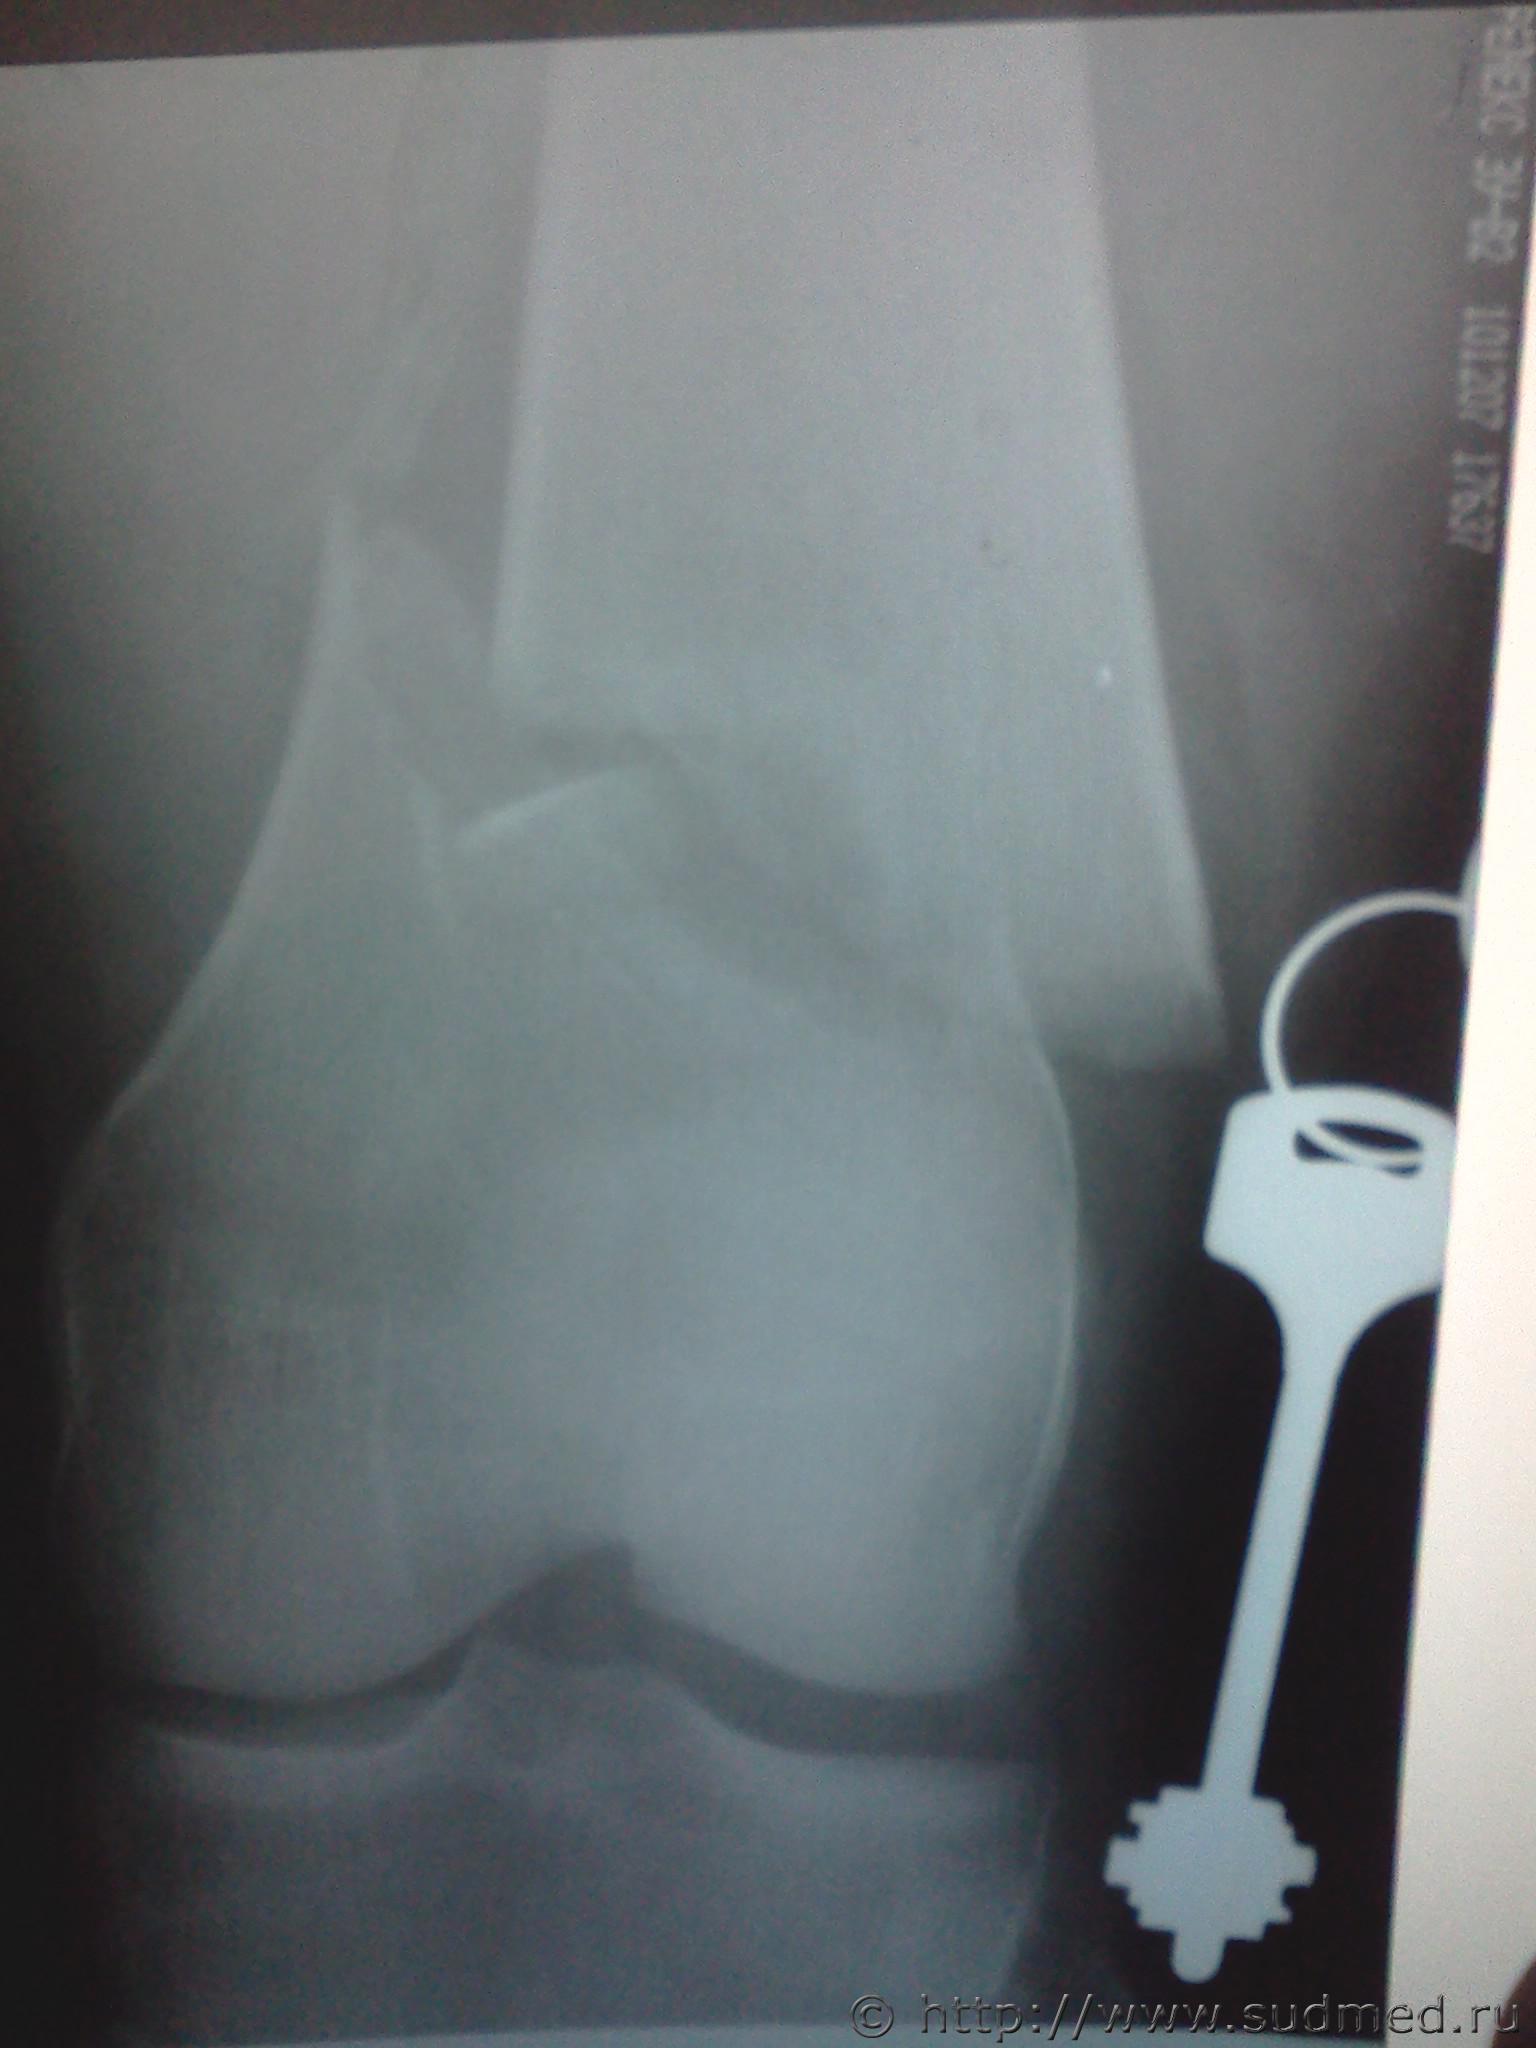

правая бедренная

левая большеберцовая

Эскизы прикрепленных изображений

Судебная медицина - Прикрепленное изображение Судебная медицина - Прикрепленное изображение Судебная медицина - Прикрепленное изображение Судебная медицина - Прикрепленное изображение

Я бы не задумываясь, отнес бы каждый перелом к тяжкому вреду.

Однозначно - тяжкий вред. Перелом диафиза в нижней трети.